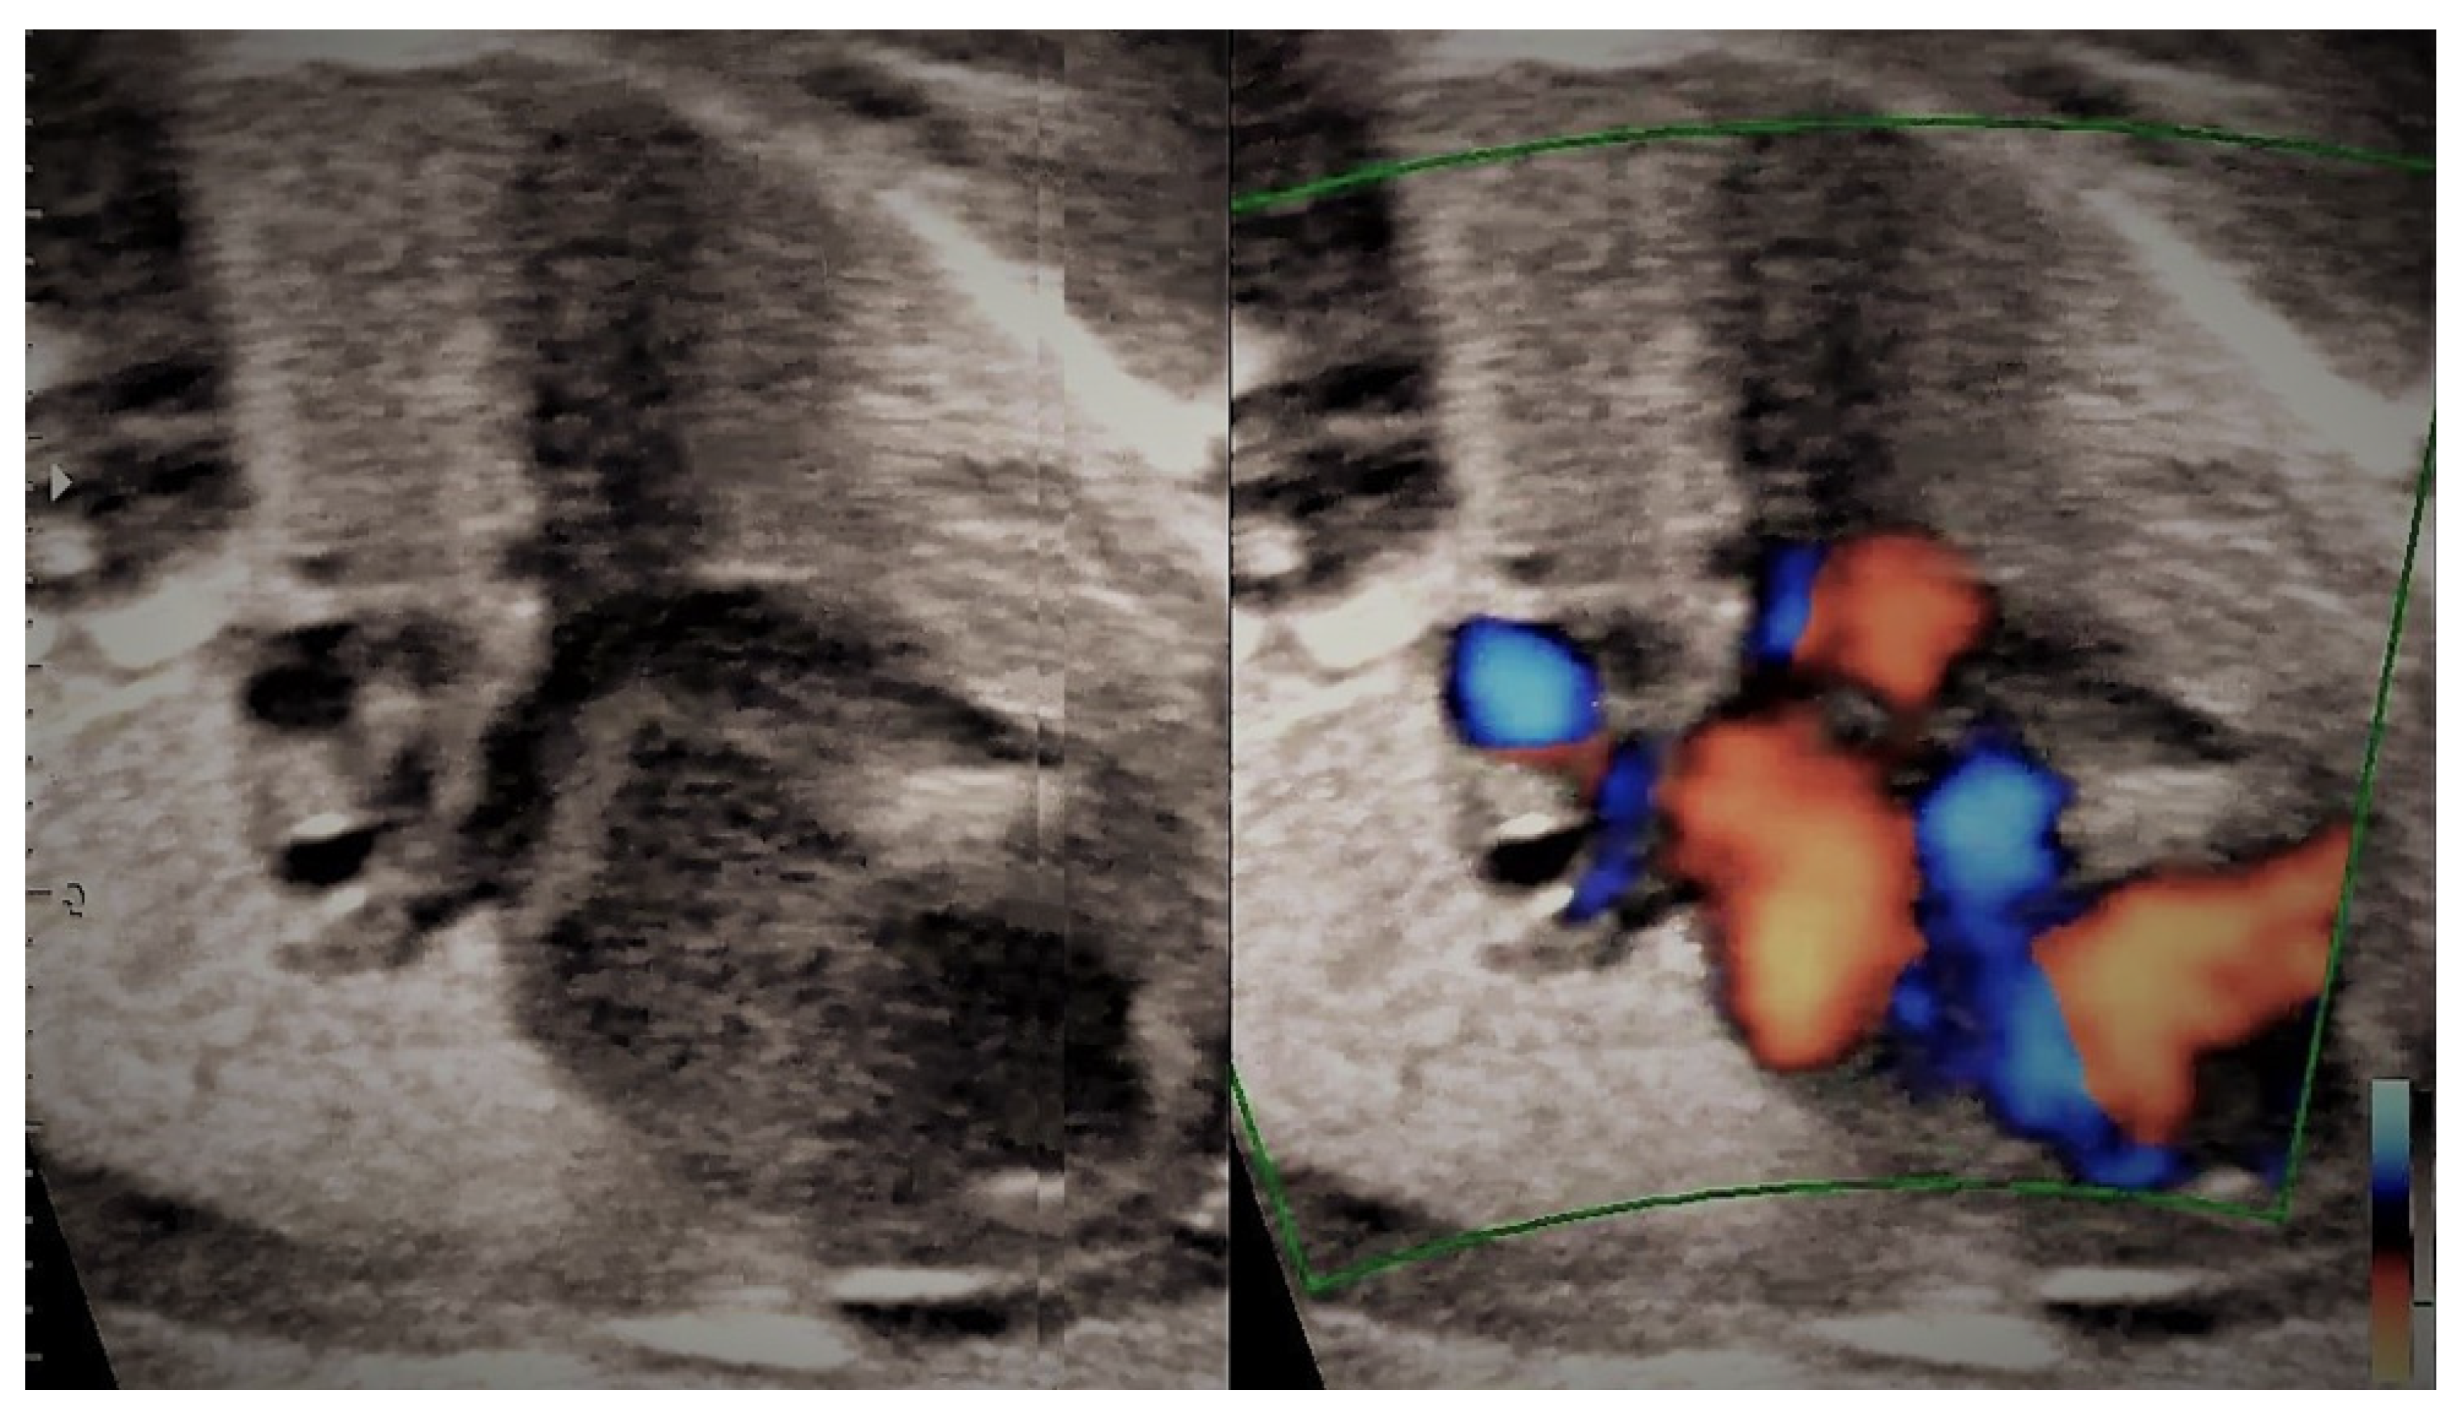

4.2. Case 2

4.3. Case 3

4.4. Case 4